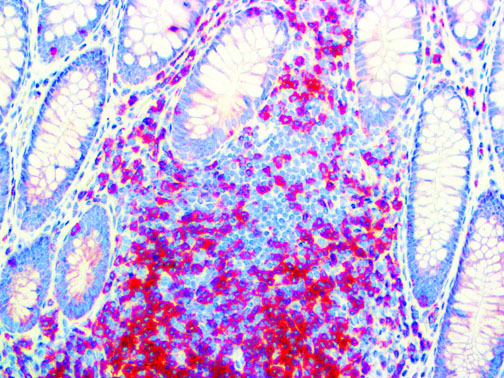

It is the ICU physician who is most likely to witness one of the deadliest manifestations of the abnormal immunological response, the cytokine storm syndrome (CSS). This response is also referred to by some as the cytokine release syndrome (CRS). CSS is characterized by continuous activation and expansion of macrophage and lymphocyte populations, which secrete large amounts of cytokines, causing the cytokine storm. This massive cytokine release is akin to hemophagocytic lymphohistiocytosis (HLH) disease, a syndrome characterized by initial unchecked and persistent activation of cytotoxic T lymphocytes and NK cells.

Clinical and laboratory manifestations of HLH include fever, enlarged liver and/or spleen, neurologic dysfunction, coagulopathy, liver dysfunction, cytopenias (i.e., low levels of erythrocytes, leukocytes, and/or platelets), hypertriglyceridemia, hyperferritinemia, hemophagocytosis, and eventually diminished NK cell activity as the immune system becomes progressively paralyzed. HLH can be familial (primary HLH) or secondary to another disease process (sHLH), such as rheumatic disease, in which it is referred to as macrophage activation syndrome (MAS, characterized by elevated ferritin).

This activation induces inflammatory monocytes to highly express IL-6, starting a localized and then systemic cascade effect that results in hyperproduction of IL-6, which accelerates the inflammatory process. Because IL-6 also increases vascular permeability, excessive levels cause blood vessels to become very leaky. This, along with clotting factors released from vascular endothelial cells, stimulates the coagulation cascade, resulting in microthrombosis (tiny clots), which leads to ischemia and tissue death of the kidney, intestines, heart, liver, brain and extremities.